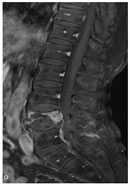

CASE 5

T1W AXIAL IMAGE SHOWING DIFFUSE DISC BULGE, LIGAMENTUM FLAVUM HYPERTROPHY AND BILATERAL FACETAL ARTHROPATHY CAUSING SEVERE THECAL SAC STENOSIS

T2W MID SAGITTAL IMAGE SHOWING MINIMAL RETROLISTHESIS OF L2 OVER L3 AND DISC DEGENERATION AT ALL LUMBER INTERVERTEBRAL LEVELS WITH REDUCED DISC HEIGHT AT FEW LEVELS. THERE IS DISC PROTRUSION NOTED AT L2-3, L3-4, L4-5 LEVELS CAUSING INDENTATION OVER THECAL SAC